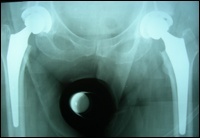

What type of hip replacement is used?

The type of bearing surface that is used depends on multiple factors such as patient age, level of activity, bone structure, allergy profile, etc. In general however the most frequenstly used bearing surface is a ceramic or metal head on a highly crosslinked polyethylene liner. These bearing surfaces are attached to the stem and cup which are inserted into the bone and are titanium based.